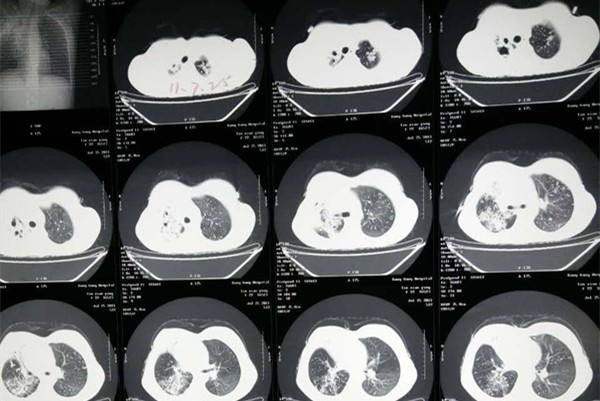

一般结核病初期症状比较轻微,不易引人注意。随着疾病进展,肺结核患者常见的全身症状主要表现为发热、盗汗、逐渐消瘦等。常见的呼吸系统症状包括咳嗽、咳痰、咯血、胸闷等。

那么患上肺结核能治好吗?目前对于肺结核的治疗服用抗结核药物是首要的一种治疗方式。初治肺结核的治疗周期一般为6-8个月,合理、规范的多药物联合治疗可以使病灶消灭,症状缓解,病情康复。但是需要谨记抗结核治疗10字原则:早期、联合、适量、规律、全程。如果治疗不规范,将会导致细菌对常见的抗结核药药发生耐受,耐药结核病的治疗成本和药物毒副作用大大增加,使得病人耐受能力下降,治疗效果往往不佳。